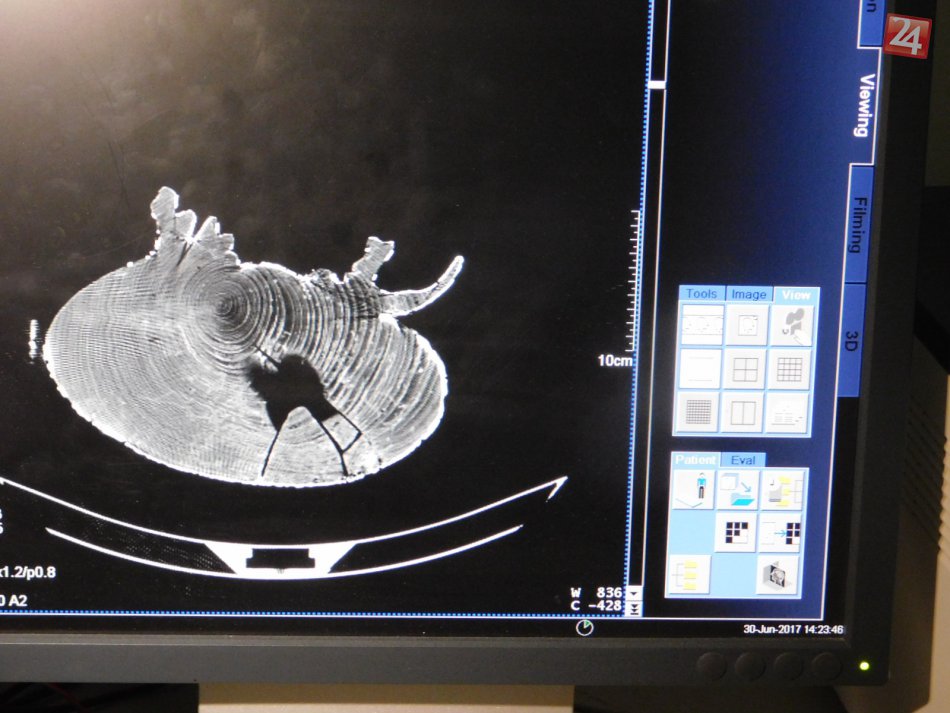

Galéria k článku To musíte vidieť: V novoveskej nemocnici absolvovali CT kuriózni pacienti!